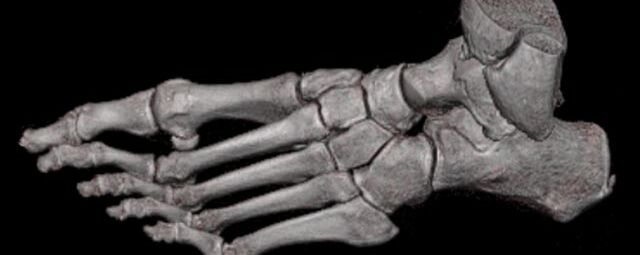

Extremitäten

• bei komplizierten Frakturen z. B. in der Nähe von Gelenken oder im Bereich der Handwurzel und Fußwurzel